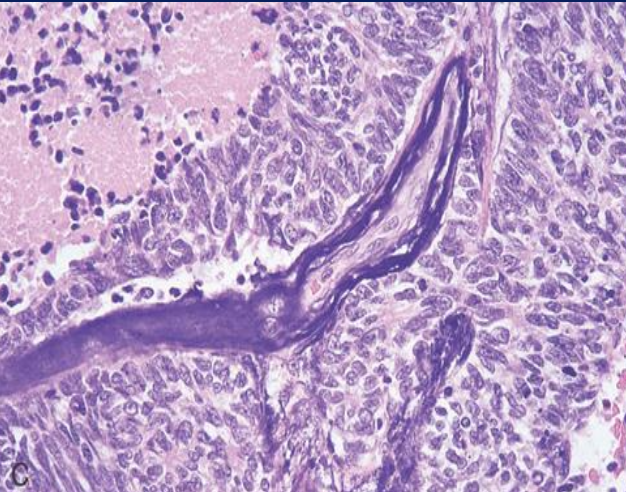

<p>EFECTO DE AZZOPARDI</p>

EFECTO DE AZZOPARDI

Tinción basofílica de las paredes vasculares debido a acumulación de ADN de núcleos necróticos